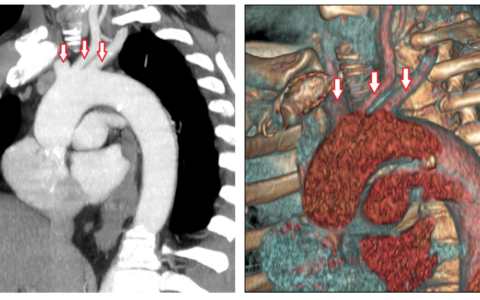

Анатомия коронарных артерий: КТ-изображения